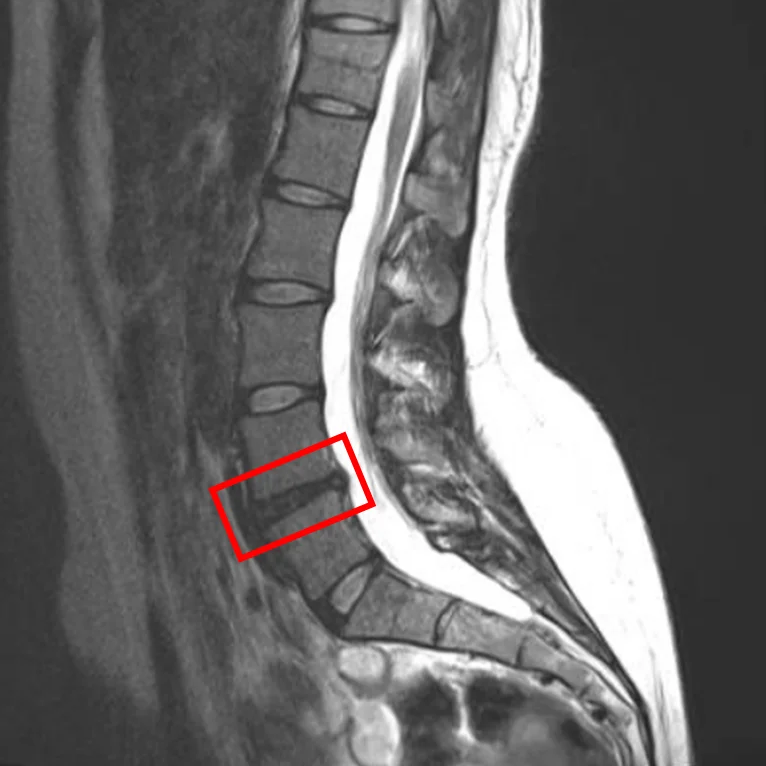

По данным МРТ и результатам осмотра пациентки выявлена грыжа межпозвоночных дисков L4/L5.

Симптомы по 10-балльной шкале (0 – отсутствие симптомов, 10 – сильные боли/онемение):

– боли в пояснице: 4;

– боли в ногах: 0;

– онемение в ногах: 2;

– боли в ягодицах: 0.